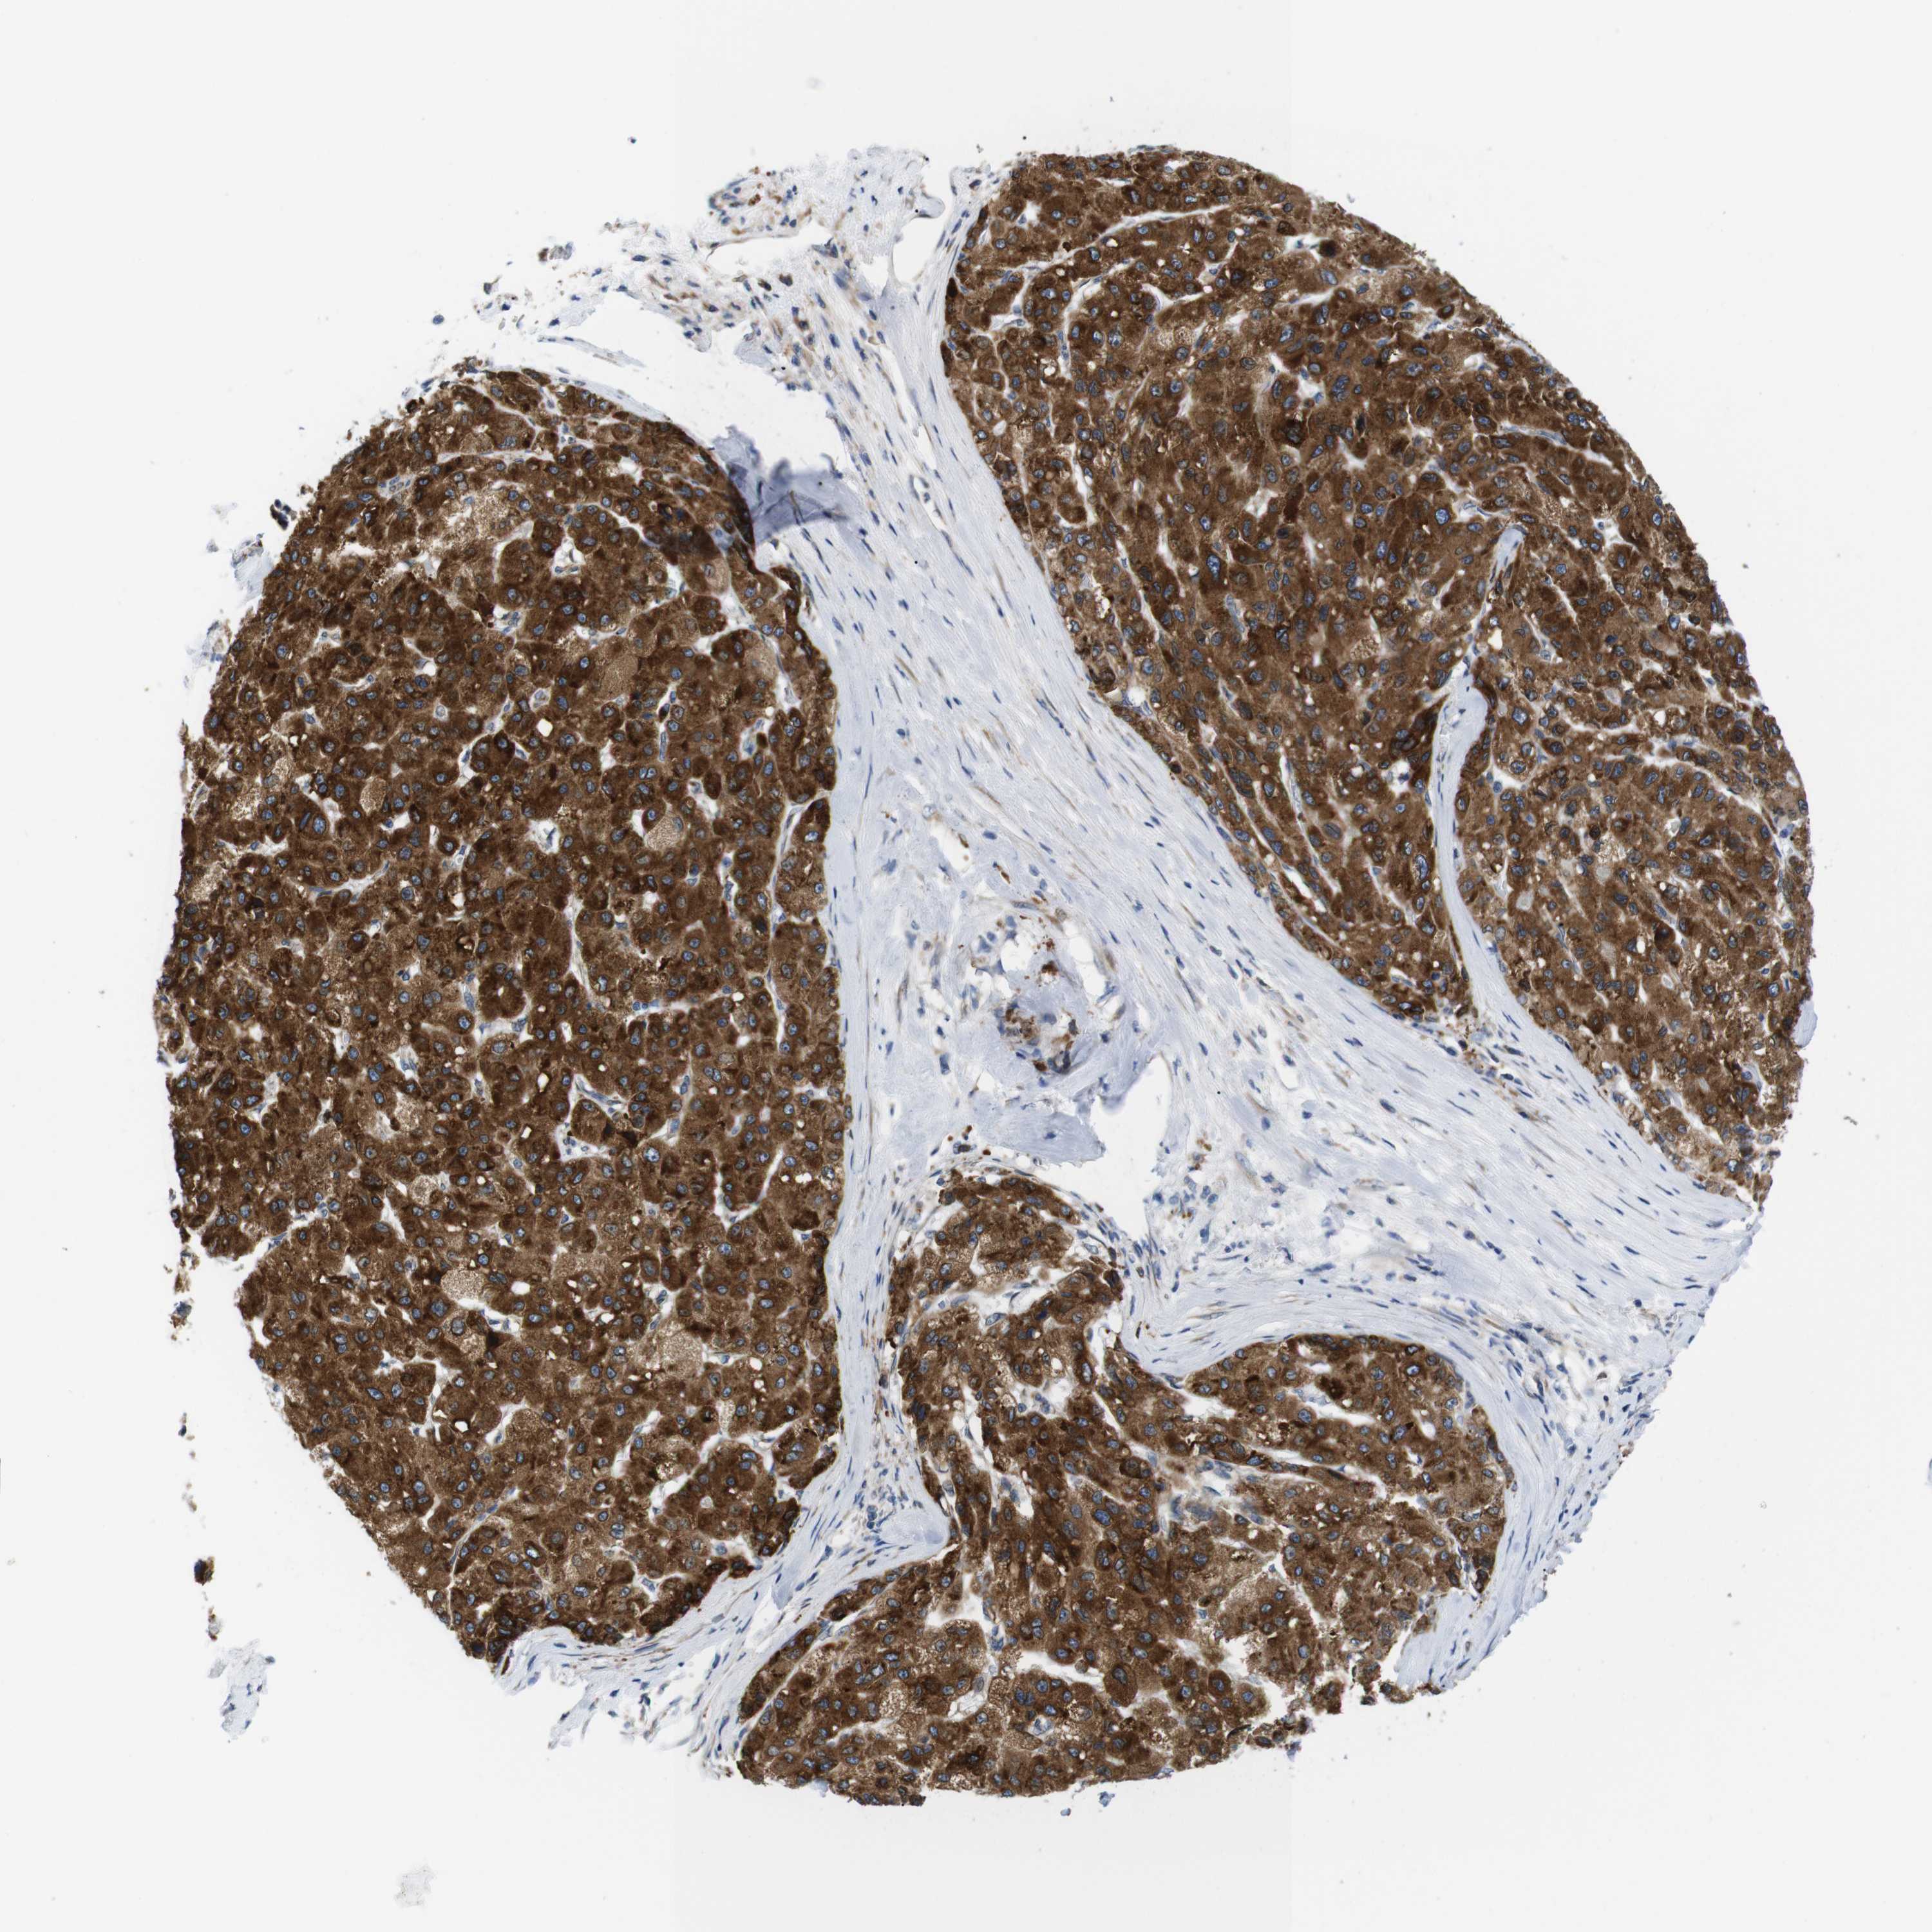

LIVER CANCER - Protein expressioni

A mouse-over function shows sample information and annotation data. Click on an image to view it in a full screen mode. Samples can be filtered based on level of antibody staining by selecting one or several of the following categories: high, medium, low and not detected. The assay and annotation is described here.

Note that samples used for immunohistochemistry by the Human Protein Atlas do not correspond to samples in the TCGA dataset.

Antibody stainingi

Antibody staining in the annotated cell types in the current human tissue is reported as not detected, low, medium, or high, based on conventional immunohistochemistry profiling in selected tissues. This score is based on the combination of the staining intensity and fraction of stained cells.

Each image is clickable and will lead to virtual microscopy that enables deeper exploration of all samples and also displays staining intensity scores, fraction scores and subcellular localization as well as patient and tissue information for each sample.

Antibody HPA014837

Staining

High

Medium

Low

Not detected

Intensity

Strong

Moderate

Weak

Negative

Quantity

>75%

75%-25%

<25%

None

Location

Nuclear

Cytoplasmic/membranous

Cytoplasmic/membranous,nuclear

Cholangiocarcinoma

Carcinoma, Hepatocellular, NOS